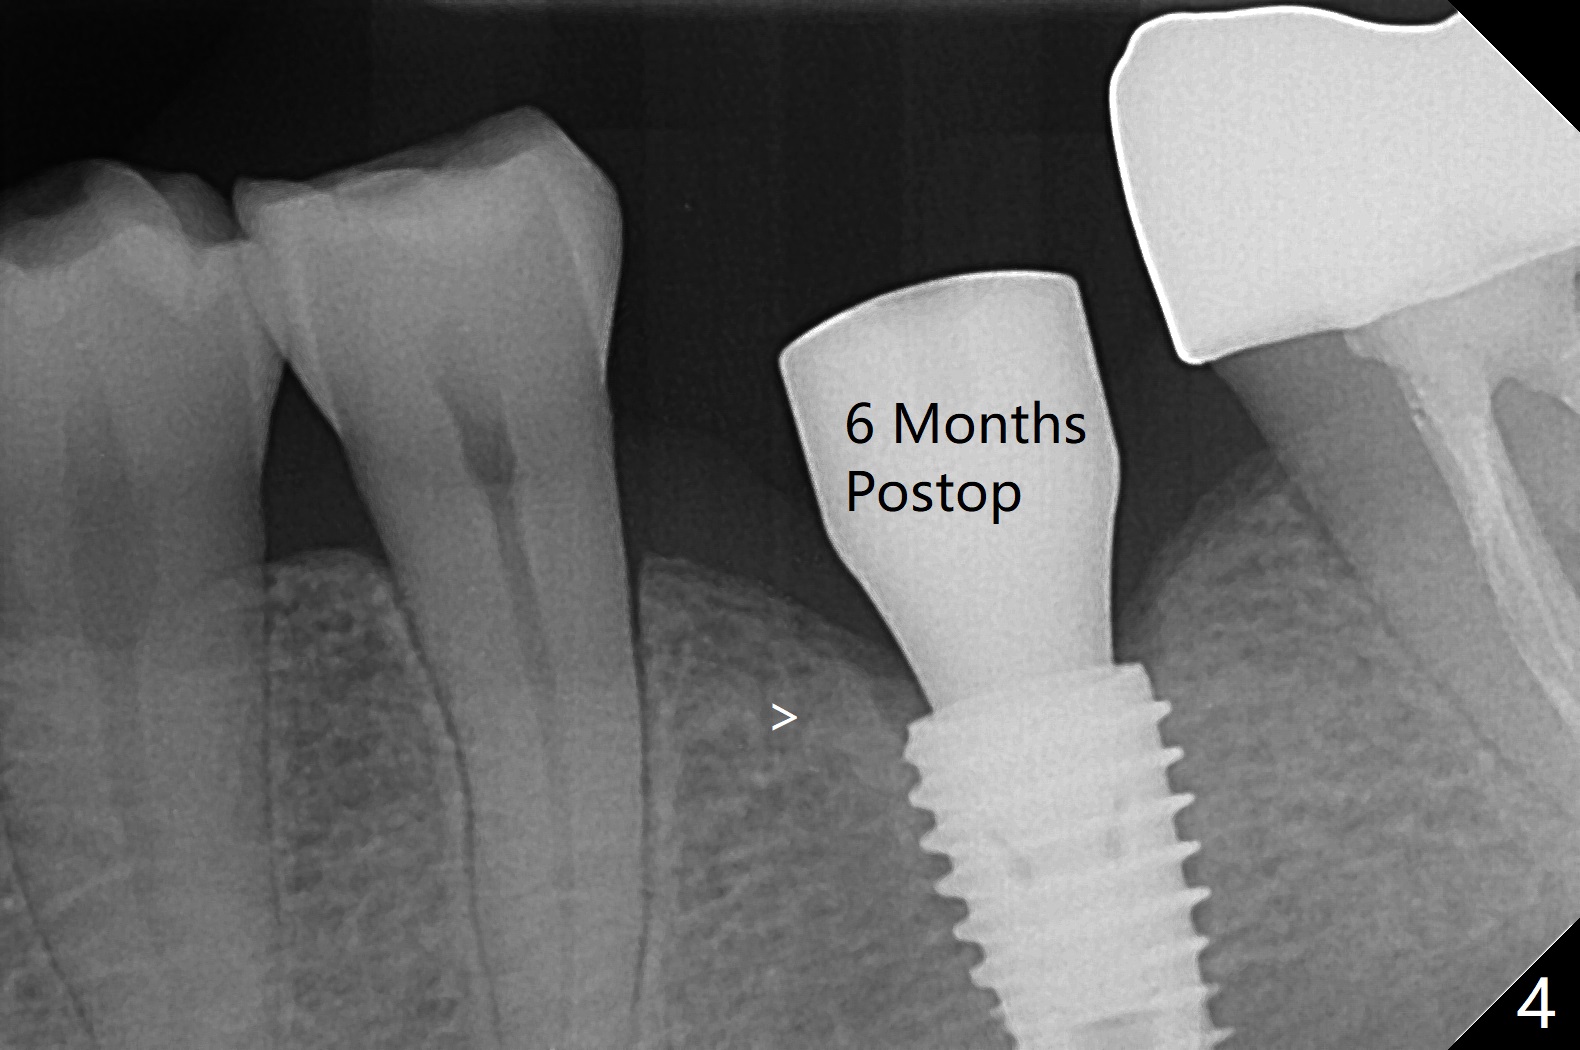

With one carpule of Xylocaine (34 mg with 17 mcg of Epinephrine), a 5x8.5 mm implant is placed at #19 in a timely and painless manner. The patient is pleased as compared to her previous implant placement at #3 and 30. Due to the thin buccal bone, the implant is placed ~.5 mm deeper than designed; a 6.5x4(2) mm healing abutment is incompletely seated (Fig.1). A smaller and skinny one (5.5x7(4) mm) is seated normally (Fig.2). Regional panoramic X-ray shows clearance from the Inferior Alveolar Canal (Fig.3 *). Although there is crestal bone resorption 6 months postop, the bone density next to the 1st thread is high (Fig.4 >). A 5.5x4(4) mm cemented abutment is placed for impression. The patient returns with #18 crown dislodgement and #19 crown loosening 11 months post cementation (Fig.5 <: gap between implant and abutment). Since the crown and abutment are unable to be torqued properly, they are removed (Fig.6). A narrower abutment is able to be seated apparently completely while a metal post (Fig.7 *) is tried in in the distal root of #18. To reduce the chance of re-fracture of #18 crown, the tooth #15 needs to be distalized orthodontically so that an implant will be placed at #14 (Fig.5).